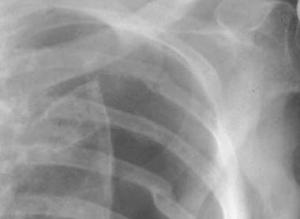

Tetralogy of Fallot (TOF) is one of the most common congenital heart disorders (CHDs). This condition is classified as a cyanotic heart disorder, because tetralogy of Fallot results in an inadequate flow of blood to the lungs for oxygenation (right-to-left shunt) (see the following image). Patients with tetralogy of Fallot initially present with cyanosis shortly after birth, thereby attracting early medical attention.